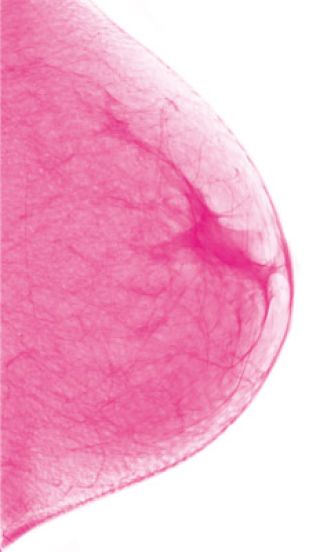

SALUD Para sacarle la careta a una enfermedad que mata cinco mil mujeres por año en la Argentina, el Primer Congreso de Pacientes de Cáncer de Mama busca generar un nuevo espacio de asesoramiento e intercambio de experiencias entre pacientes en tratamiento, pacientes recuperadas, familiares y médicxs especializadxs. El 70 por ciento de los casos se detecta en el autoexamen y el 75 por ciento no tiene antecedentes familiares, de manera que la prevención es la mejor aliada.

El cáncer de mama es la proliferación acelerada, desordenada y no controlada de las células del tejido mamario. En la actualidad, toda mujer debe controlarse. Atrás queda el reducir a un grupo la posibilidad de desarrollar la enfermedad, ya que entre los factores de riesgo figuran los antecedentes personales y familiares de cáncer de mama o de enfermedad benigna (no cancerosa) de mama y tratamiento con radioterapia u hormonas, pero también el sobrepeso, el sedentarismo, el tabaquismo y el consumo de alcohol en exceso. Asimismo, se calcula que afecta a una de cada ocho mujeres y el mayor factor de riesgo es ser mujer, ya que en el 75 por ciento de los casos ocurre en mujeres sin ningún factor de riesgo conocido. Hasta acá, la alarma parece extenderse y crecer, sin embargo, como se aclara desde el Centro Mamario del Hospital Universitario Austral, la clave de la enfermedad está en la prevención: el 70 por ciento de los tumores se detecta en el autoexamen.